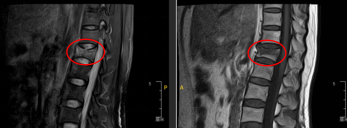

术前MR